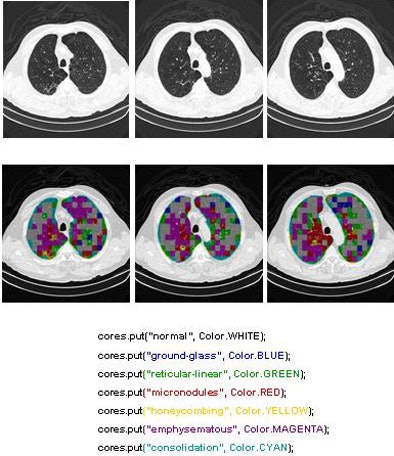

![]() |

| The classification algorithm training and test was performed using a 10-fold cross-validation methodology, which classified regions of interest in the lung parenchyma into nine patterns commonly seen on thoracic high-resolution CT images. The background and outside tissue classes indicate regions outside the lungs, while the remaining seven classes refer to patterns found in the lungs: normal parenchyma, ground-glass opacities, reticular and linear opacities, nodular opacities, honeycombing, emphysematous change, and consolidation. The classification step delivered an initial average accuracy of 61.6% (above). Eliminating the two most frequently confused categories, ground-glass opacities and consolidation, improved the average classification accuracy to 78%. |

| The completed CAD-analyzed cases are stored as a new series in the PACS server, where they can be examined side by side. In the color-coding system, normal parenchyma is white; ground-glass regions are blue; reticular-linear, green; micronodules, red; honeycombing, yellow; emphysematous changes, magenta; and consolidation, cyan. |